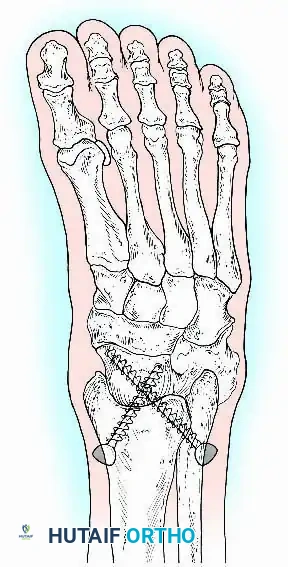

Internal Fixation

Internal fixation is currently the preferred method for uncomplicated ankle arthrodesis due to higher union rates, superior patient comfort, and the elimination of pin-tract infections. Biomechanical studies demonstrate that crossed, large-diameter (6.5 mm or 7.3 mm) cannulated cancellous screws provide exceptional resistance to shear and torsional forces.

A standard construct involves two or three screws:

1. A "home run" screw directed from the posterior malleolus into the anterior neck of the talus.

2. A screw from the medial malleolus into the lateral body of the talus.

3. A screw from the anterolateral tibia into the medial talar body.

For complex hindfoot reconstructions, specialized plating systems, including anterior or lateral locking plates, can be utilized to supplement screw fixation, particularly when structural allografts are required to restore limb length.